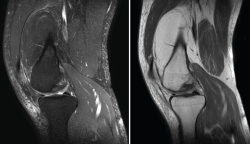

1.2.2. Ligamento cruzado anterior (LCA) (Figuras 40, 41, 42, 43 y 44)

Figura 40. Corte de secuencia sagital T2 Fat-Sat de resonancia magnética de rodilla: ligamento cruzado anterior normal.

Figura 41. Cortes de secuencia sagital T2 Fat-Sat de resonancia magnética de rodilla: rotura central del ligamento cruzado anterior.

Figura 42. Cortes de secuencia sagital T2 Fat-Sat: rotura proximal del ligamento cruzado anterior.